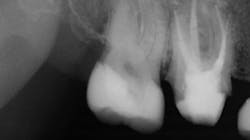

Because of the controversy and confusion about whether posts increase the strength of endodontically treated teeth, our research organization tested that subject. The results are available in the May 2004 issue of Clinicians Report (CR). Research showed that properly placed posts of any type available at the time increased the strength of endodontically treated teeth. Therefore, set that controversy aside. Posts strengthen teeth despite some contrary reports in the literature (figures 1 and 2).When should we use posts?